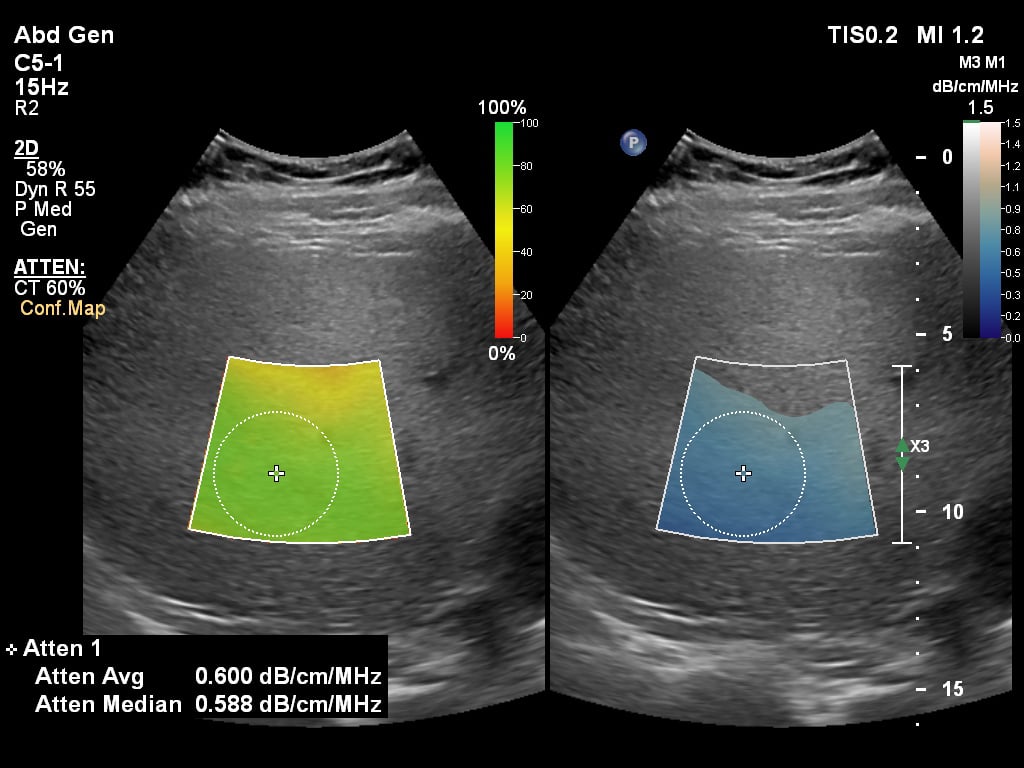

Philips Healthcare Epiq Ultrasound GI Liver

The Philips liver fat quantification tool.